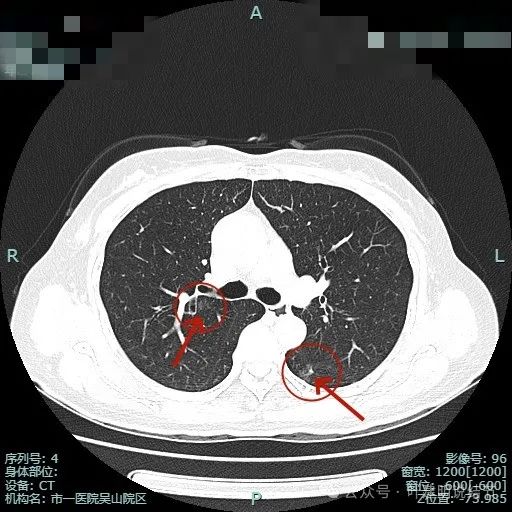

左下叶背段病灶出现(病灶1),靠叶间裂,密度不纯,若单此层当然并不一定是恶性,也可能是慢性炎的。

胸膜似略有牵拉密度不纯。